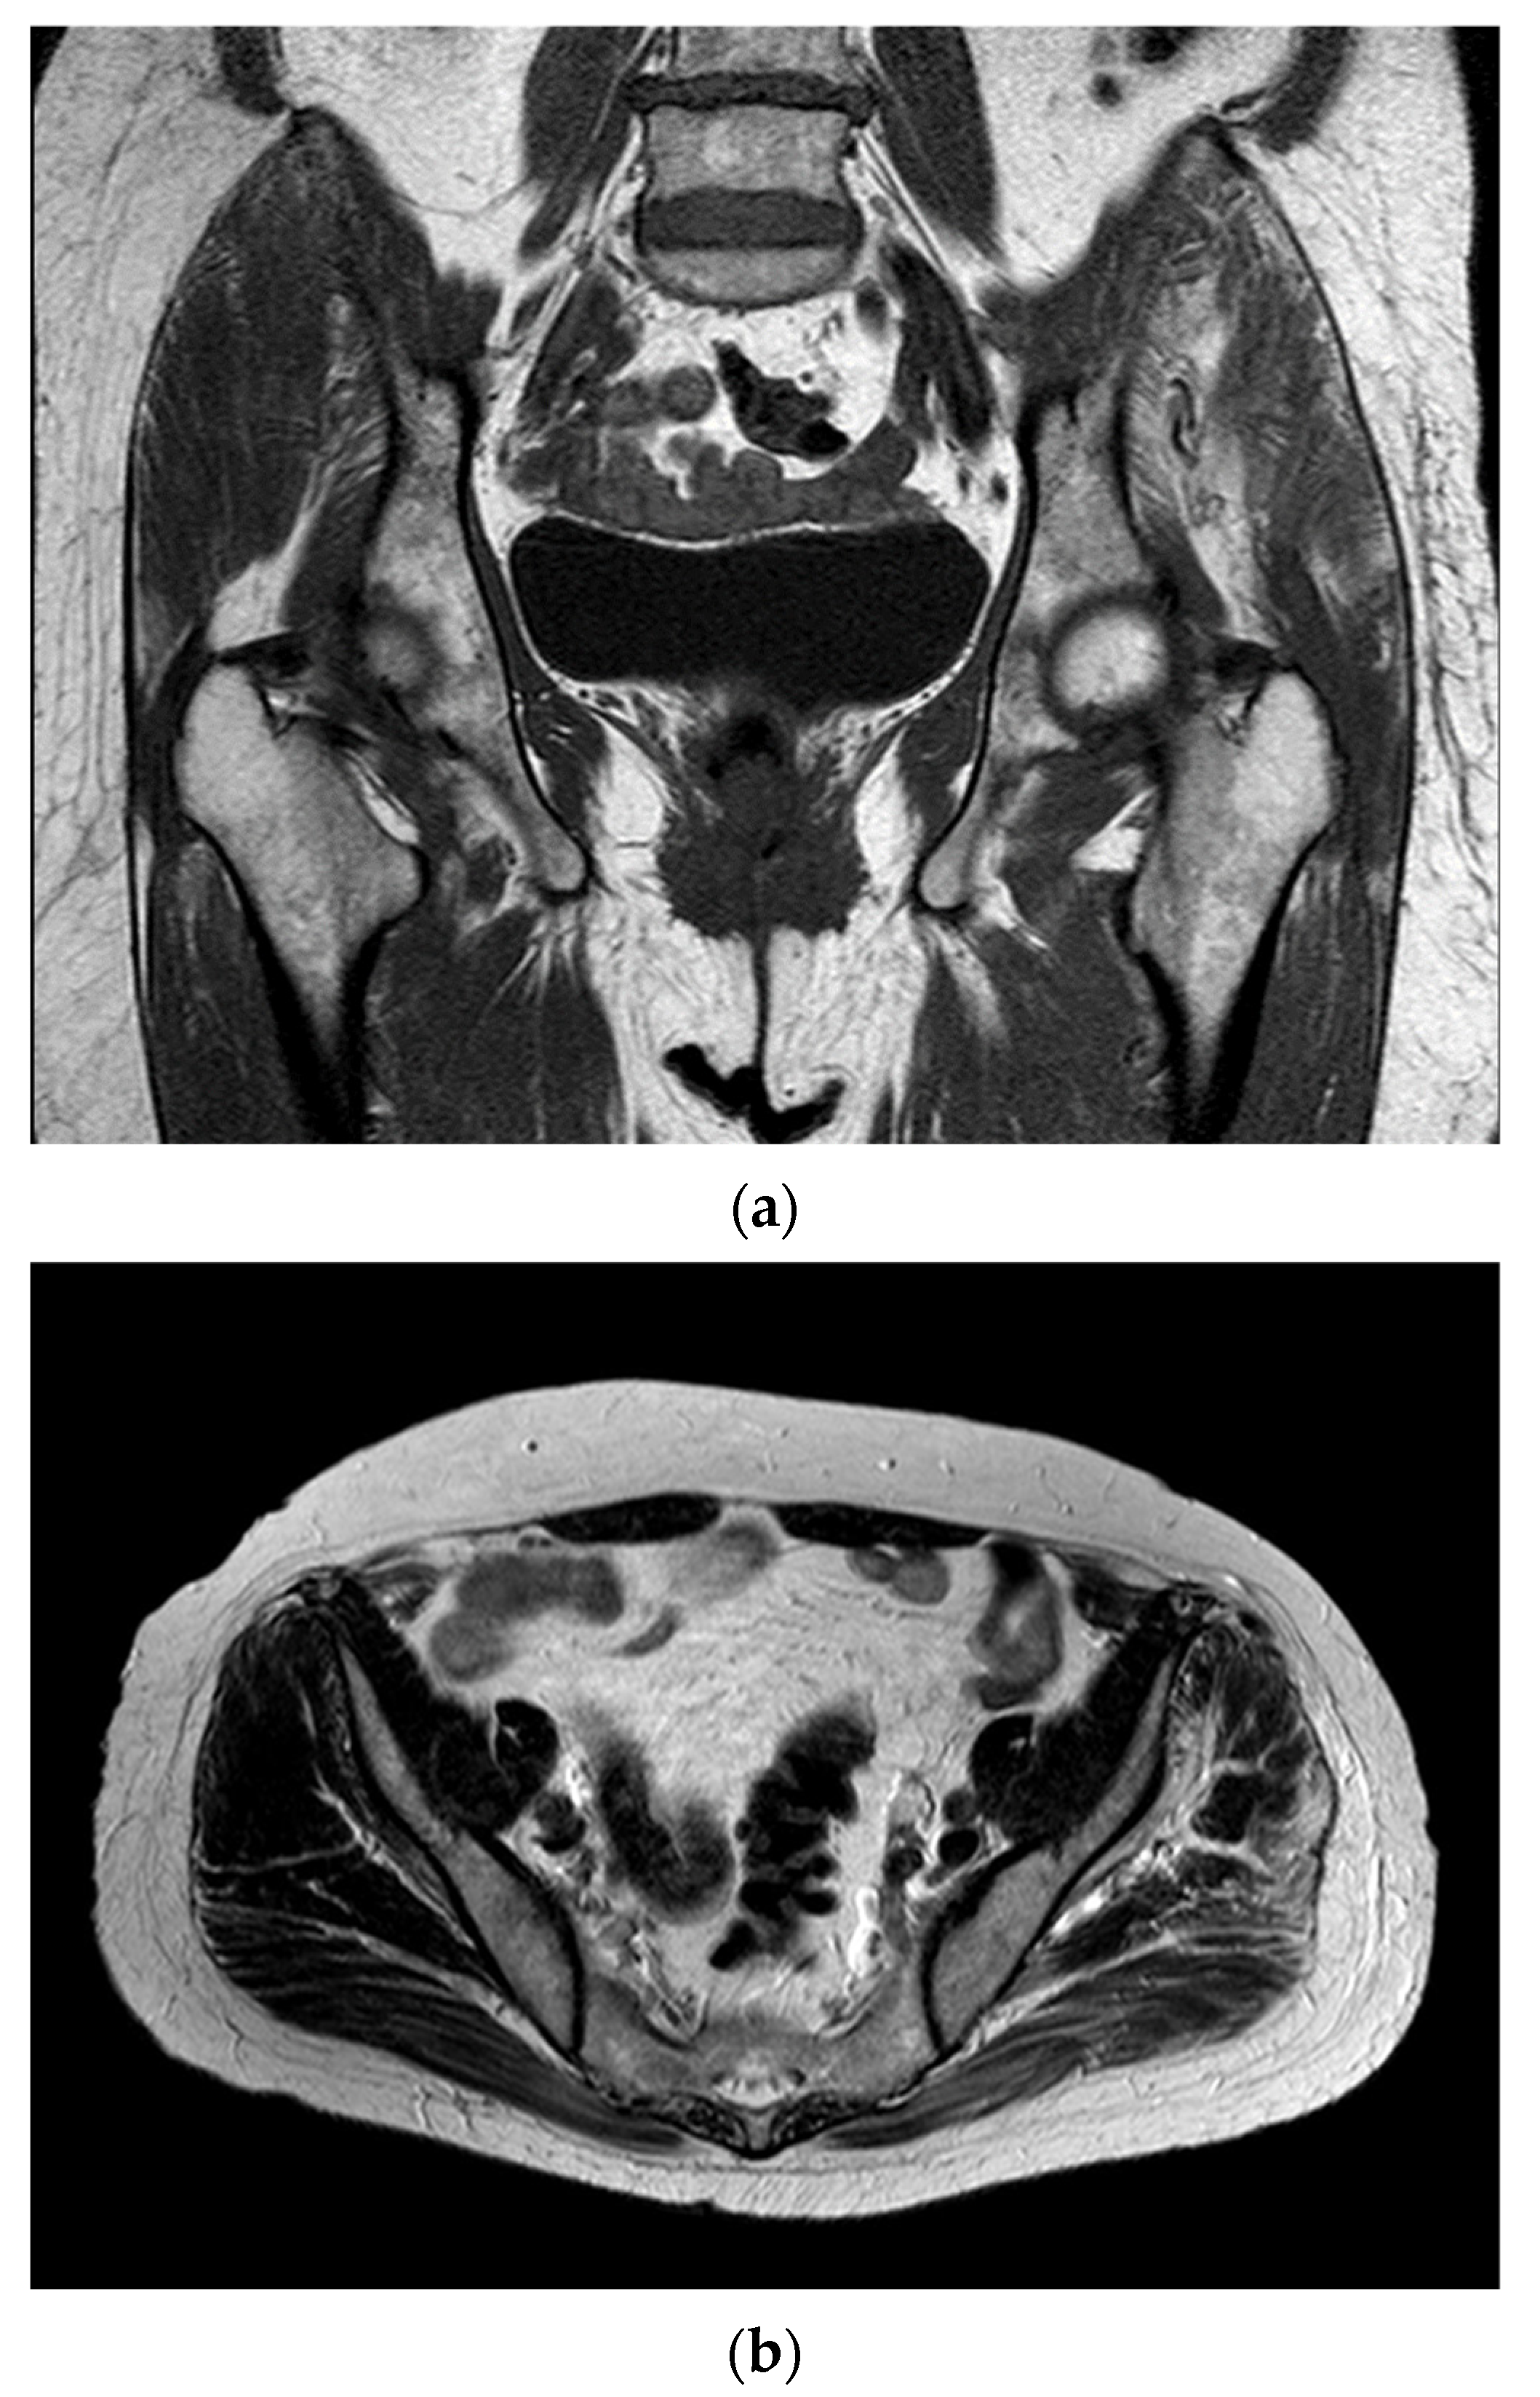

2. Case Report